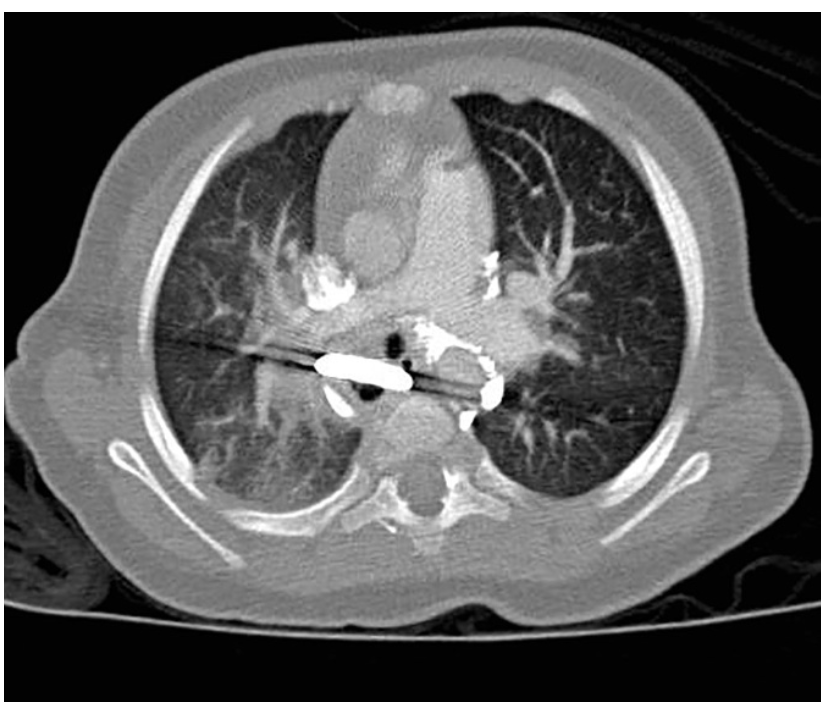

And possibly due to some weird impulse that seems to have travelled across space and time itself, the patient gets an X-ray which shows a button battery and there is just enough in the story to make people look a little harder with a CT scan.

And it’s fair to say that a patient with symptoms of complications possibly weeks down the track a moment for pause is required. Partly because finally we’re back at the part of the talk that is actually about acquired tracheo-oesophageal fistula. Which was supposed to be the point I recall.

Perhaps the thing to do at this point is actually to take a step back from acquired TOF specifically and talk more broadly about anaesthesia for tracheo-oesophageal fistula. It turns out that there isn’t necessarily a lot of agreement on what you should do. A little while back Knottenbelt et al looked retrospectively at TOF anaesthesia across 101 patients in the Oz/NZ context. In their series, 32% had an IV induction, 68% had an inhalational anaesthetic and 64% of the patients were maintained with spontaneous ventilation until control of the fistula.

That’s the standard plan anyway. Question 2 is maybe less relevant in congenital TOF but really important in acquired ones because the tissues are probably going to be pretty awful for the surgeons to deal with and the risk of things falling apart. At least in a congenital case there is likely to be some options for oxygenating/ventilating useful bits of lung. If it falls apart here, that may not be so easy to produce restoration of oxygenation/ventiation.

And this may well be why a discussion about doing the whole procedure with cardiopulmonary bypass comes into the mix for these patients. It is described in this Hofmeyr paper, and it is likewise described in a paper covering multidisciplinary care in both the congenital and acquired scenario. In that series 100% of the acquired cases (5/7 being button batteries) were done with cardiopulmonary bypass.